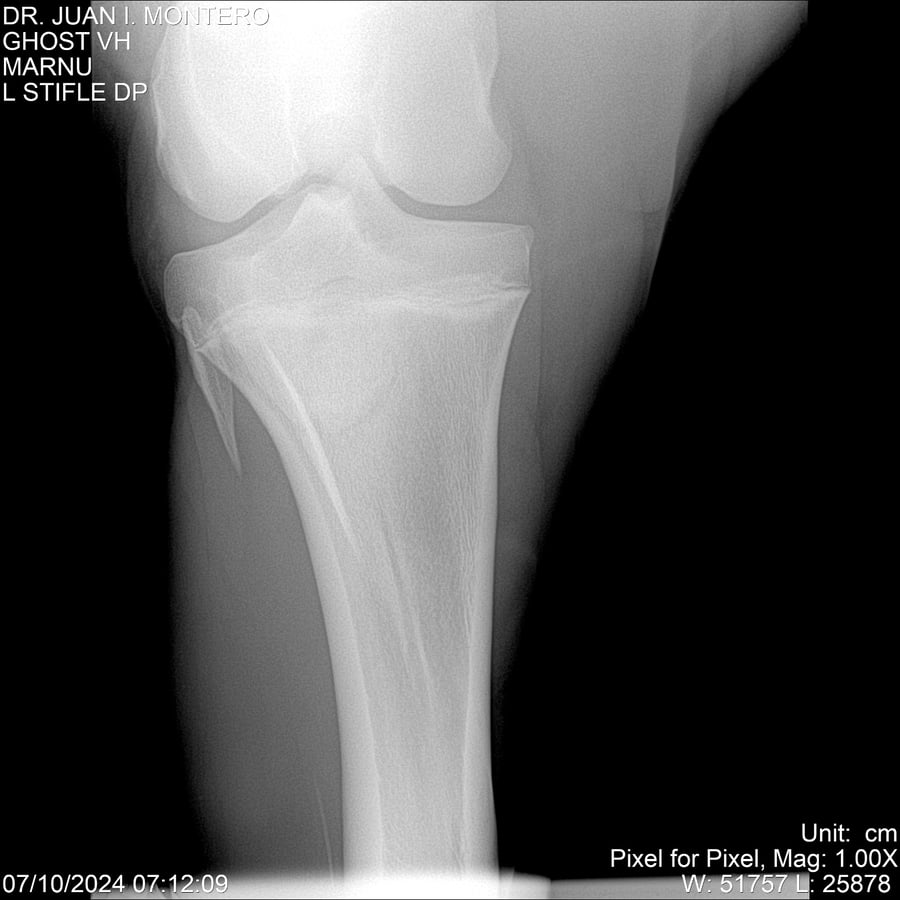

LOTE 15, GHOST VH 🔥 🔥 🔥 Lote Anterior Volver al remate Lote Siguiente Ficha Contacto Montevideo - Ficha del Lote Identificador: #282525 Categoría: Yeguarizos Montevideo - 69 Visualizaciones ClicData Contacto Empresa: Abelenda N. R., Walter Hugo Nombre*: Teléfono* : E-mail* : Mensaje Enviar Registrese gratis Este contenido Exclusivo está disponible sólo para usuarios registrados Ingresar